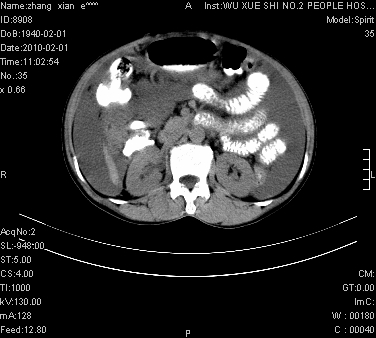

标题: CT24434:70岁 女 腹胀,腹水原因待查 [打印本页]

标题: CT24434:70岁 女 腹胀,腹水原因待查

大量腹水,脾脏囊性占位,子宫颈占位,右侧腹股沟淋巴结肿大,建议+c,先查妇科。

腹盆腔大量积液,子宫增大,子宫颈增大外形不规则,内见低密度影,膀胱后壁显示不清,右腹股沟肿大淋巴结,脾脏囊性占位,子宫颈占位,子宫颈癌?建议增强。

考虑:1、腹膜转移,大量腹水;

2、脾占位性病变;

3、左侧卵巢占位性病变,建议增强进一步检查。